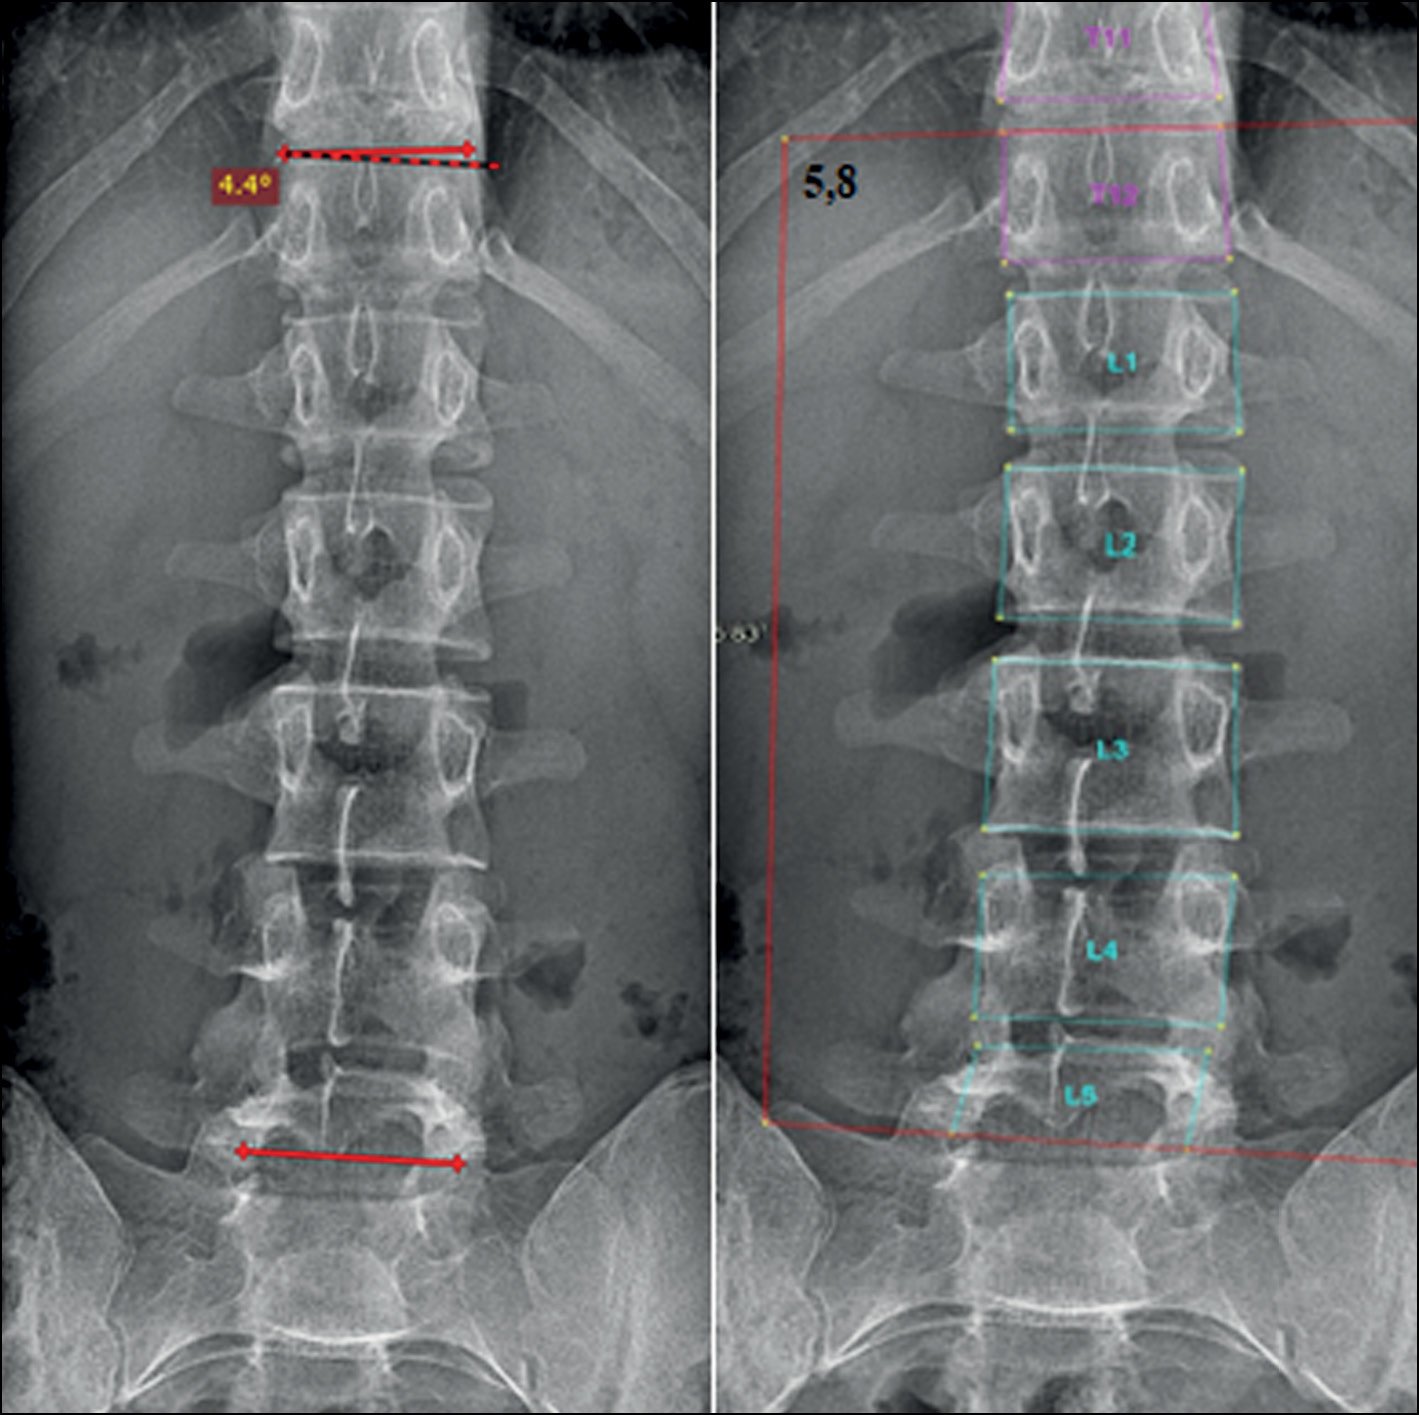

In addition, when using the program, the radiologist can change vertebral markings made by the system automatically. This is very essential to overcome any errors in vertebral markings that can cause a false final result. Further analysis of the results showed that the inaccurate marking of vertebral bodies and their borders predominantly led to less accurate results of angle measurement and scoliosis grade definition. This was mainly seen when evaluating scoliosis in poor-quality images and CXR images. The borders of the midthoracic vertebrae in CXR images usually are not seen posterior to the mediastinum. Multiple normal CXR images (grade 0, defined by the radiologist) were recognized by the system as grade 1 scoliosis because of detecting an FP curve (proximal or midthoracic curve) (Fig. 5). Other common error was also seen in marking the borders of L5 vertebral body (Fig. 6). The adjacent bony structures (adjacent sacrum and iliac bones) limit the definition of L5 borders, particularly its lower endplate.

Fig. 5. Errors in vertebral markings on radiographs with grade 0 (normal). In CXR images, poor definition of the vertebral borders may lead to false measurements.

Fig. 6. Errors in vertebral markings on radiographs with grade 0 (normal). Errors in defining the L5 vertebral body may lead to false positive curve detection (left).

Regarding errors in evaluating images with group 0 scoliosis, most of the measurements by the AI system resulted in angles with >5° but very close to it. However, such minimal variability in measurements between the system and the radiologist led to a change in the grade from 0 to 1 (Fig. 7). The majority of such angles (70%) were found in the range of 5°–6°, as shown in the pie chart (Fig. 8).

Fig. 7. Errors of the system in evaluating images with grade 0 scoliosis. Cobb’s angles measured by the radiologist (left) and the AI system (right). Measurement variability is not significant (1.4°); however, the scoliosis grade is 0 by the doctor and 1 by the system.

Fig. 8. Distribution of angles measured by the AI system on normal X-ray images; 70% of the 5°–6° range.